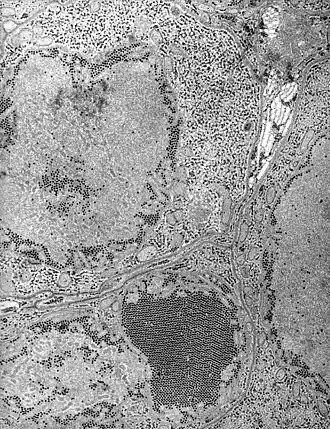

Микрофотография возбудителя инфекции

Возбудитель заболевания является флавивирус группы В, переносчиками которого служат комары рода Culex, а резервуаром — птицы (воробьи, голубые сойки и голуби), в меньшей степени млекопитающие. Вирус размером около 20—30 нм, хорошо переносит замораживание, высушивание. При нагревании до 56 °C быстро разрушается. Комары размножаются в стоячей, загрязненной органическими отходами воде, питаются человеческой кровью, залетая в дома. Активизируются в темное время суток. Распространен как в Северной Америке, так и в Южной. Сезонность заболевания — июль—сентябрь. Регистрируется обычно у лиц старше 35 лет. Входными воротами инфекции является кожа. Вирус после укуса комара распространяется по организму гематогенным путём, поражая внутренние органы, в особенности центральную нервную систему[3][5].